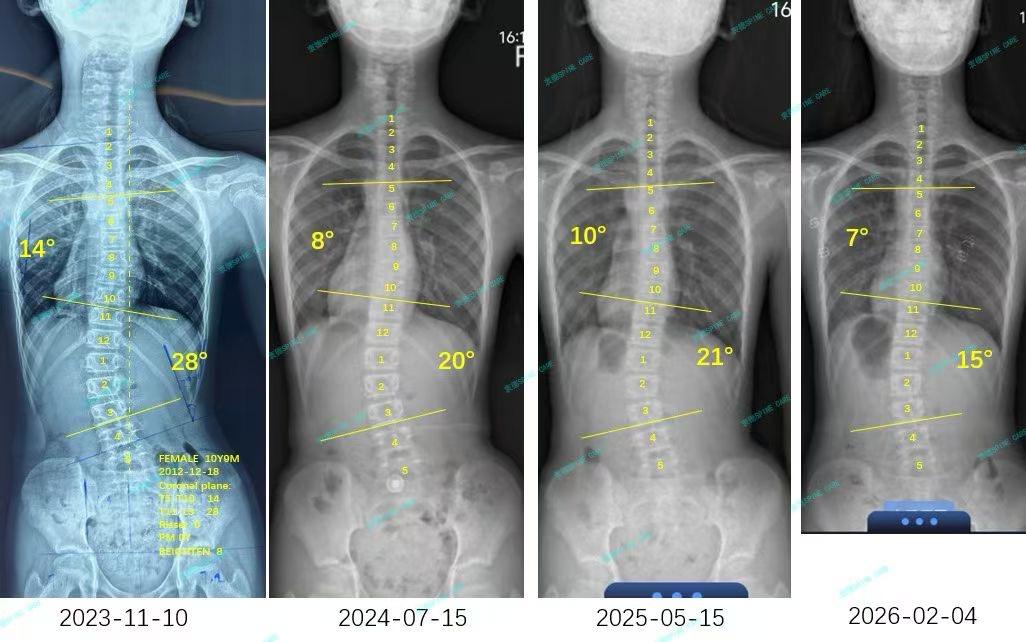

我是甜甜,28度到15度,我做到了~

案例主人:甜甜 发现侧弯年龄:13岁 侧弯情况:Cobb角度28度

我在这里开始了我的康复之旅,每天坚持训练,还按照杨博士的建议戴上了支具。时间过得真快,转眼两年过去了,最近我脱掉支具去拍片,结果简直太棒了!我的28度腰弯降到了15度,胸弯也从14度降到了7度。

I started my recovery journey here, training every day and wearing braces as recommended by Dr. Yang. Time flies so fast. Two years have passed in the blink of an eye. Recently, I took off my braces to take a photo shoot, and the results were amazing! My 28-degree waist bend dropped to 15 degrees, and my chest bend dropped from 14 degrees to 7 degrees.